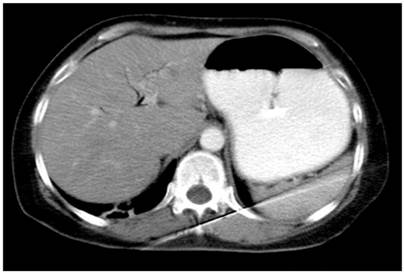

The abdominal CT scan showed intestinal obstruction as an intraluminal image in the first 4.5 x 3 cm duodenal portion (Figure 1 and 2). It was associated with pneumobilia and contrasted bile duct passage. This meets the criteria of Rigler’s triad. In addition, upper digestive tract endoscopy showed dilatation of the gastric chamber secondary to obstruction of the duodenal lumen and an impacted calculus in the duodenal bulb (Figure 3 and 4).